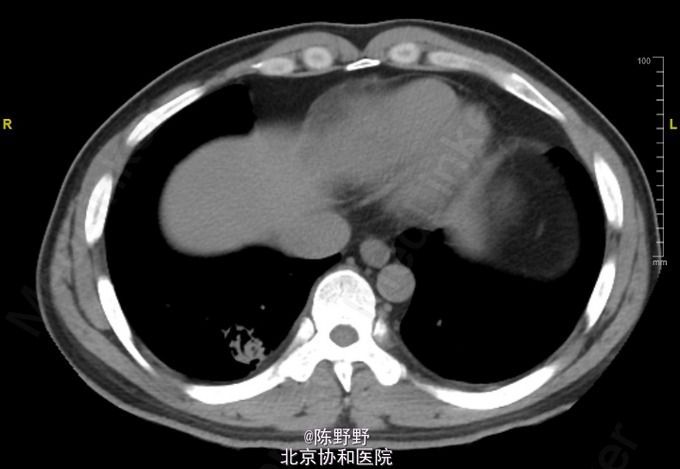

咳嗽、痰中带血丝半年

无特殊 CT提示右下肺空洞内见团状物

术前诊断考虑曲霉菌球,恶性病变不能除外 行VATS右肺下叶切除,术中切开见囊性病变内灰黑色团状病变,考虑曲霉菌球,最终病理明确诊断